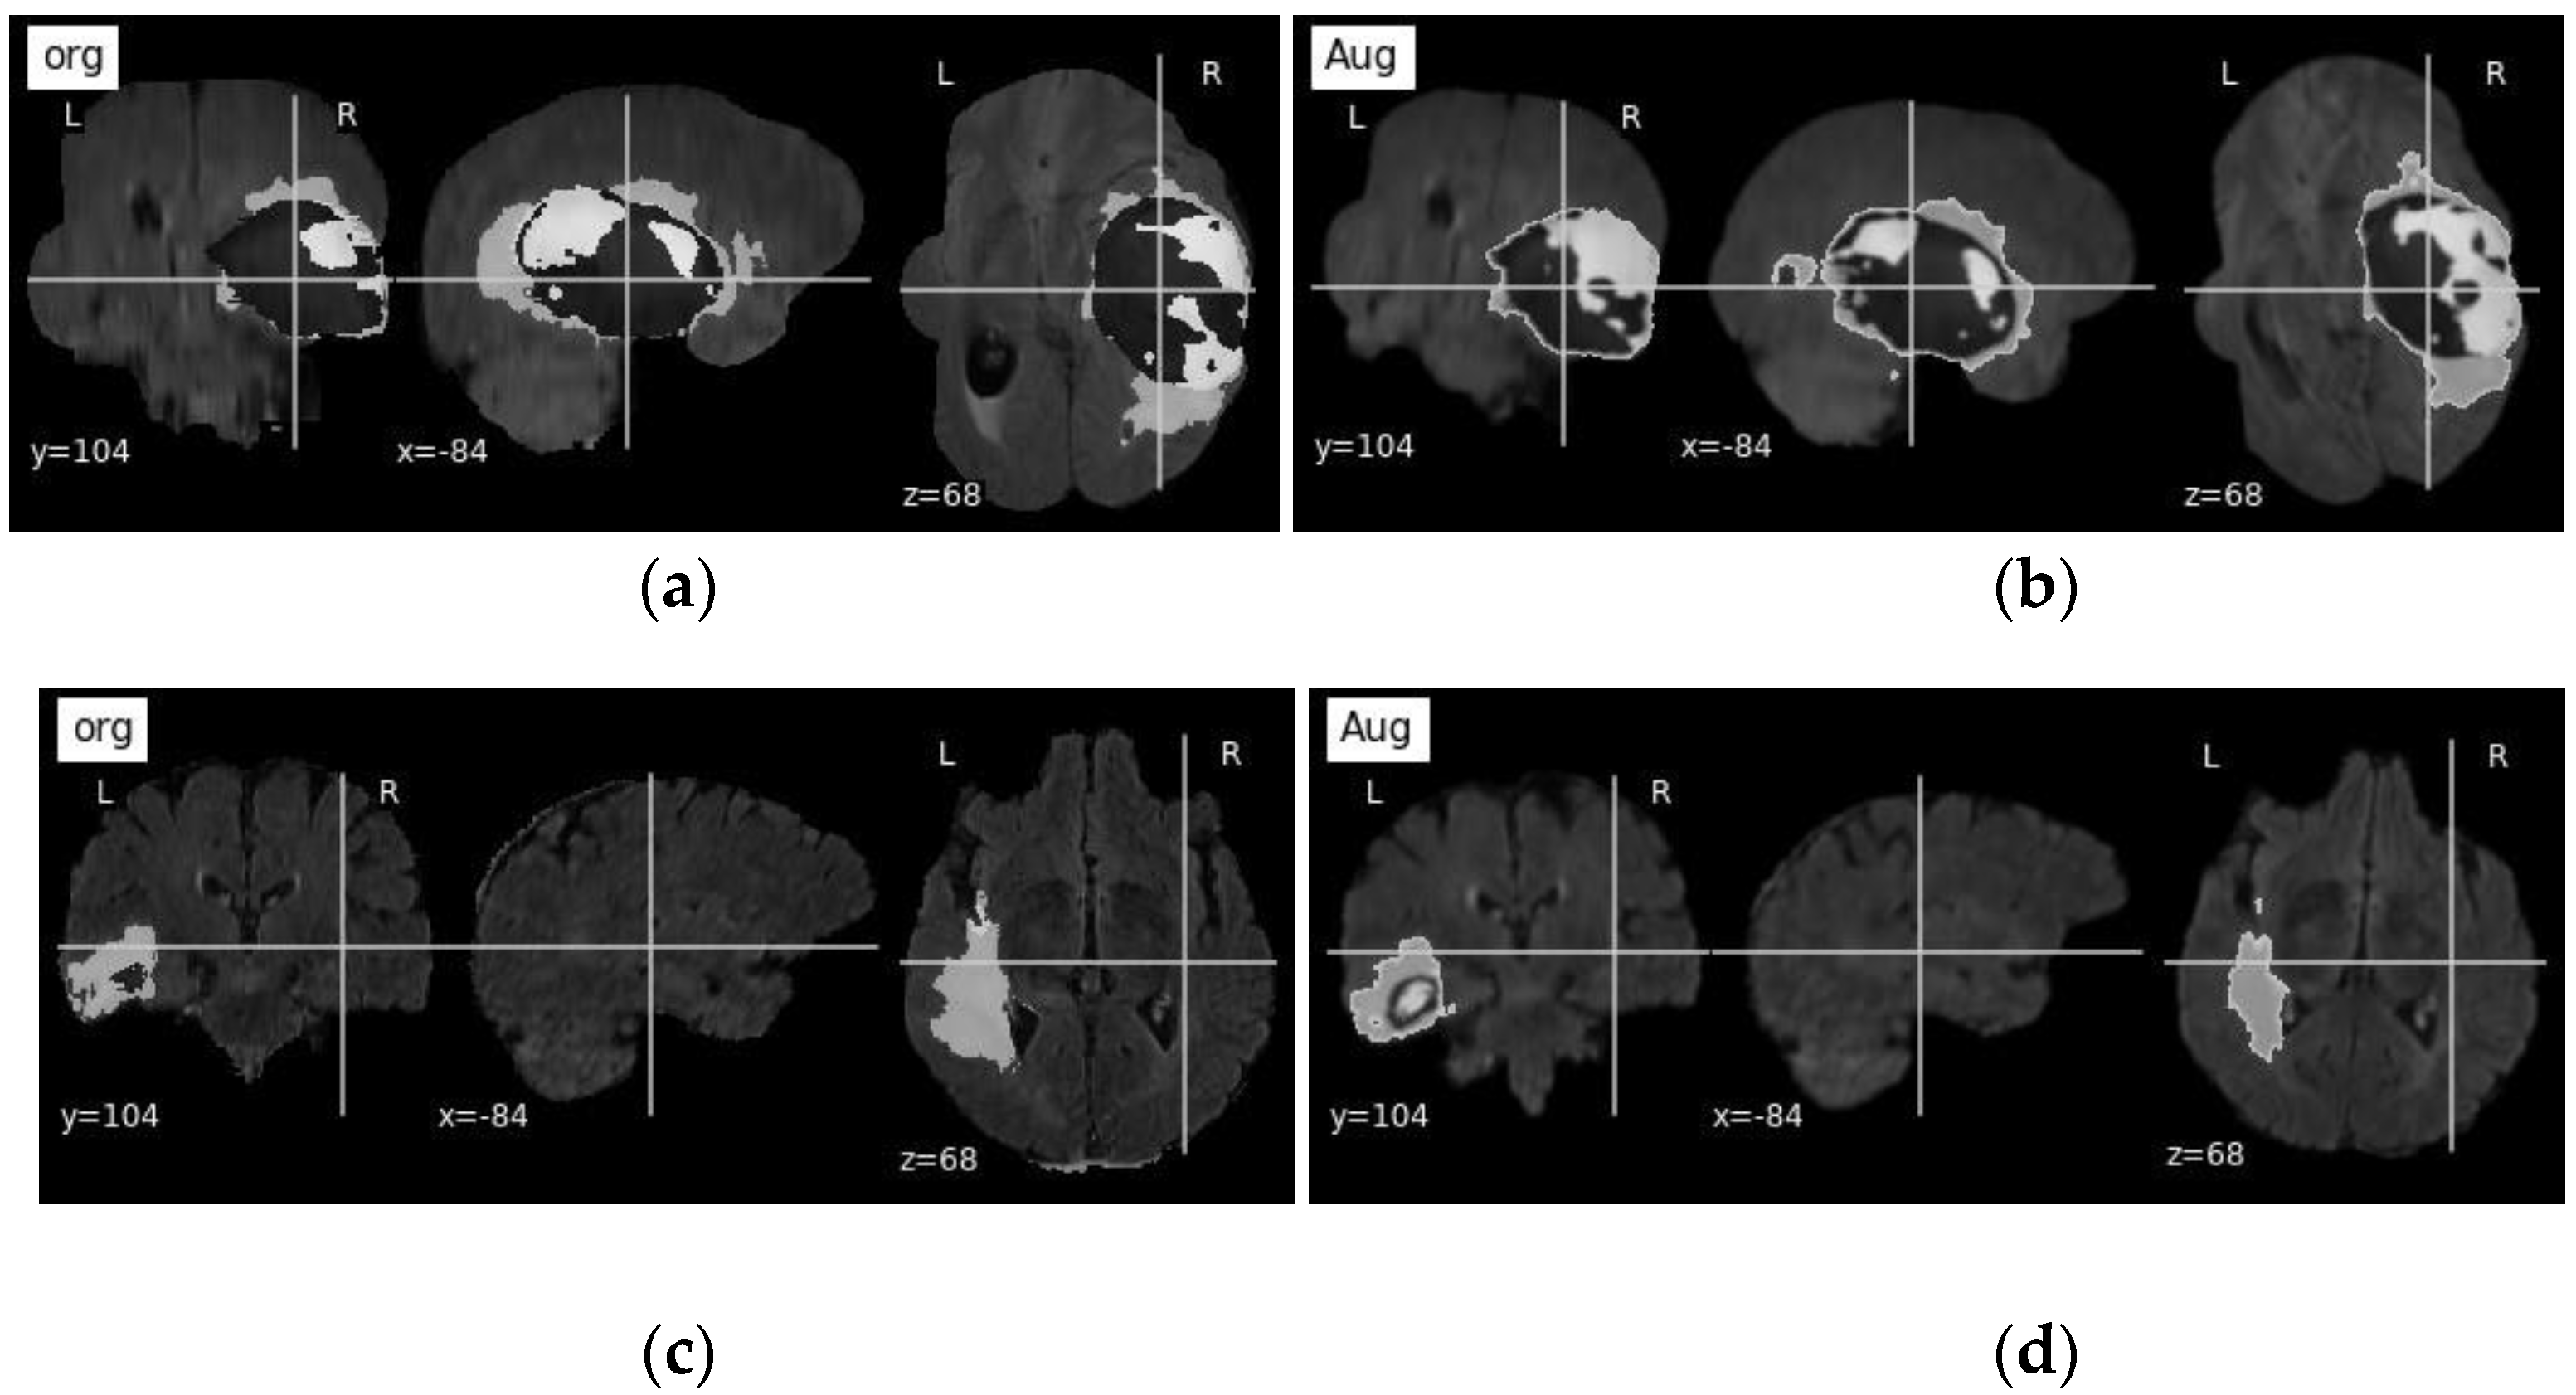

3.1. Dataset and Pre-Processing